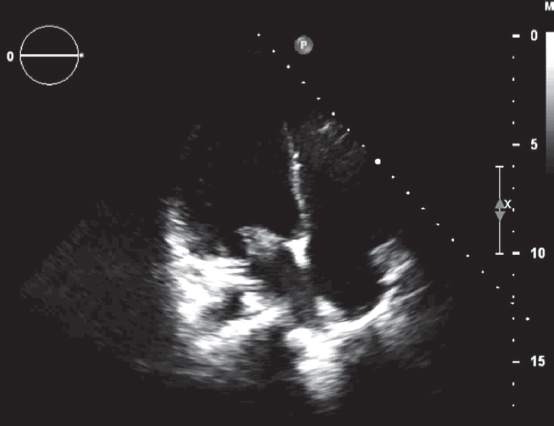

По результатам ЭхоКГ от 31.12.14 — сократительная способность миокарда сохранена. Фракция выброса левого желудочка 65 %. Камеры сердца не расширены. В области передней и задней створок митрального клапана визуализируются крупные и множественные мелкие вегетации. Недостаточность митрального клапана 1–2-й степени. Относительная недостаточность трикуспидального клапана 1–2-й степени. Умеренные явления перикардита (рис. 3, 4).

Рис. 3. Эхокардиограмма пациентки А., 16 лет. Апикальная 4-камерная проекция. Вегетации на передней створке митрального клапана

Fig. 3. ECHO of 16-year old female patient A. The apical 4-chamber view. Vegetations on the aortic leaflet of mitral valve